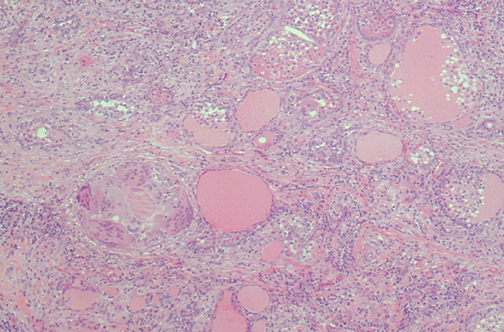

Image 8.1

Describe the histologic features. Is this process neoplastic, hyperplastic, or inflammatory?